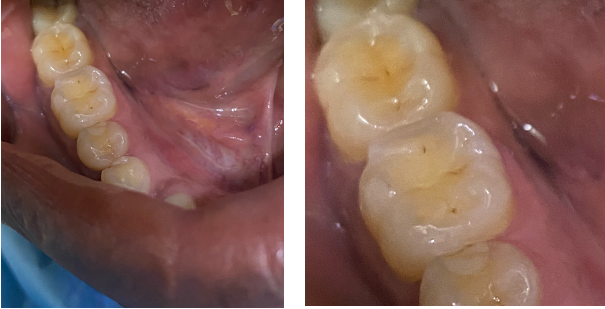

The BRUXi index, a tool proposed by Orthlieb and Duminil was used to determine the intensity of bruxism [24]. The BRUXi index is a score obtained from elements collected during the interview and clinical examination. The value of the index is obtained by adding the BRUXiq score (score obtained via the self-questionnaire) to the BRUXiex score (score obtained by collecting information in the clinical assessment). BRUXi = BRUXiq + BRUXiex. The intensity of sleep bruxism was defined as follows: low bruxism = BRUXi<20; moderate bruxism: 20<BRUXi<30 (Figure 1) and severe bruxism: BRUXi≥30 (Figure 2).